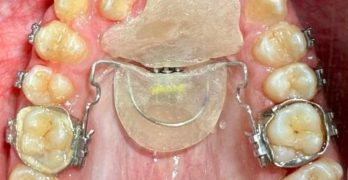

La importancia de los aparatos de expansión maxilar para la modulación del crecimiento craneofacial

El dia de hoy compartimos un artículo de nombre “Modulating craniofacial growth: The role of maxillary expansion … [Leer más...] acerca de La importancia de los aparatos de expansión maxilar para la modulación del crecimiento craneofacial